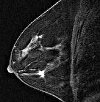

МРТ молочных желез. Неинвазивная методика диагностики, позволяющая получить четкое изображение ткани молочной железы за счет электромагнитного поля и усиления контрастности. МРТ с внутривенным контрастным введением обеспечивает патологические новообразования и сосуды, которые их питают, позволяя оценить размер и местоположение опухолей, различить их доброкачественный или злокачественный характер, обнаружить увеличенные лимфатические узлы Усовершенствованное усиление контрастности повышает прогностическую силу МРТ в обнаружении рака молочной железы до 90-95%.

МРТ молочных желез может выполняться в двух вариантах: без контрастного (нативного) и контрастного фона. Плотность грудной ткани, кистозные массы, расширенные молочно-кишечные протоки, гематомы и разрывы грудных имплантатов определяются с помощью нативной МРТ. МРТ-контраст направлен на выявление локализации, размеров и характера опухоли, а также на выявление гипертрофических лимфатических узлов.